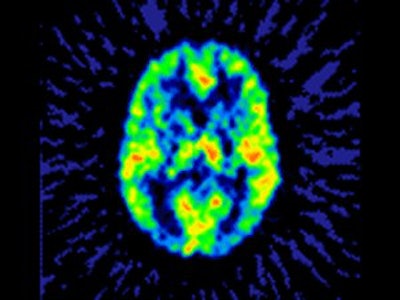

![]() |

| A functional PET scan from a subject with neuropathic pain. Note the relatively low blood flow in the left portion of the thalamus, the region that receives input from the painful zone. The decreased blood flow is a consistent finding from several different types of chronic pain. Image courtesy of Robert Coghill, Ph.D. |

"One issue that we wish to emphasize is that this study does not indicate that functional imaging studies should be used to assess pain. We know that different forms of chronic pain elicit poorly understood patterns of cerebral blood-flow changes (the marker for neural activity in many functional imaging studies)," he added. "Such blood-flow changes are inconsistent with those evoked by acute pain and are inconsistent with what we know from single-neuron recording studies in animal models of pain. Thus, the self-report of pain should remain the gold standard when making treatment decisions based on the magnitude of pain."